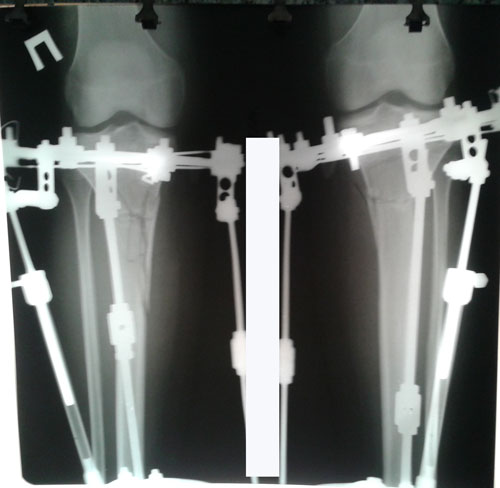

5-ый день круток.

У пациентки выраженная ротация слева.